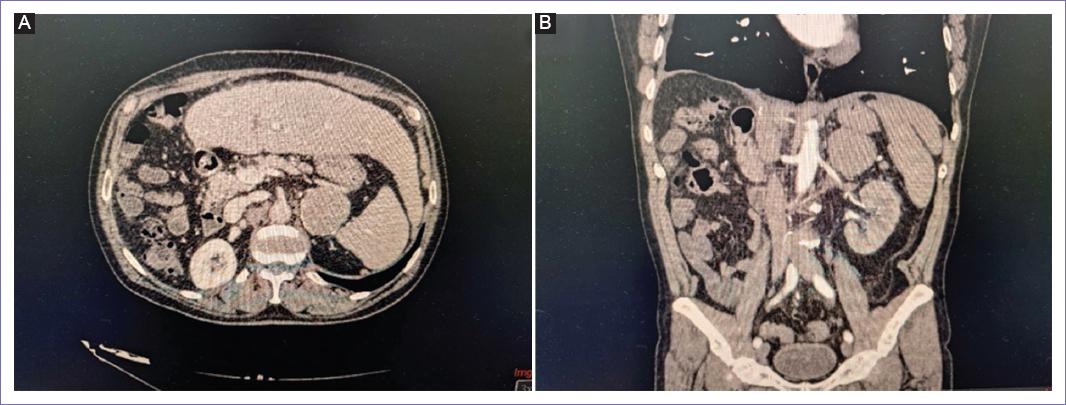

Posteriormente se realiza vigilancia con tomografía (Fig. 3), sin tener ninguna complicación para la realización de esta y acudiendo adecuadamente a su cita de control donde se evidencia, ocho meses después de la intervención primaria, tumor en glándula suprarrenal izquierda homogénea, que mide 52 x 47 mm en sus ejes máximos, por lo que se propone resección quirúrgica sospechando de metástasis de primario conocido o como diagnósticos diferenciales segundo primario por ser del lado contralateral o adenoma de glándula suprarrenal.

Figura 3 A: imágenes coronales por tomografía abdominal contrastada donde se evidencia tumor a nivel de glándula suprarrenal izquierda. B: tomografía axial de abdomen en fase contrastada tumor de glándula suprarrenal izquierda en cercanía con bazo y cola de páncreas.